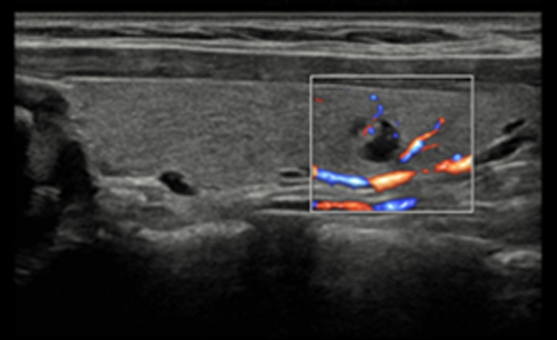

S-Flow , o tehnologie de imagistică Power Doppler direcțională, ajută și la detectarea vaselor de sânge periferice. Vă permite să faceți diagnostice precise atunci când examinarea fluxurilor sanguine este deosebit de complexă.

MV-Flow oferă imagini color avansate pentru vizualizarea structurilor microvasculare cu curgere lentă. Rata de cadre ridicată și filtrarea avansată permit MV-Flow să ofere o vizualizare detaliată a fluxului sanguin spațial.

LumiFlow este un software pentru vizualizarea tridimensională a fluxului sanguin, care vă permite să identificați în mod intuitiv structura vaselor de sânge de orice dimensiune .